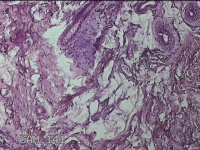

左侧会阴部皮下结节

性别

女

年龄

45岁

临床诊断

皮下结节

一般病史

发现左侧会阴部皮下结节2年余,伴近日局部隐痛不适。

标本名称

大体所见

灰白暗红色结节0.8x0.7x0.3cm一个,表面糜烂。

图4